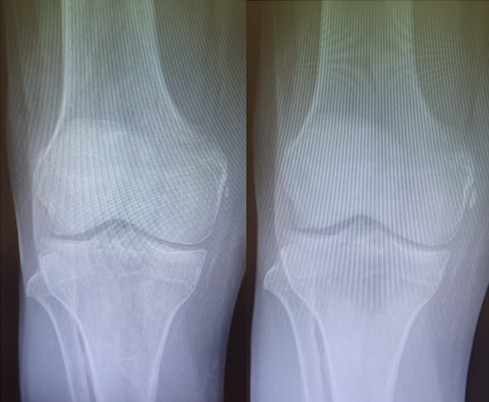

Dos ejemplos de Enfermedad de Pellegrini -Stieda.

La enfermedad de Pellegrini–Stieda se caracteriza por la osificación o calcificación postraumática del ligamento colateral medial (LCM) de la rodilla, habitualmente en su inserción femoral. En las radiografías se observa una imagen lineal o curvilínea adyacente al cóndilo femoral medial. Cuando este hallazgo se asocia a dolor, rigidez o limitación funcional, se denomina síndrome de Pellegrini–Stieda (Contreras, 2003).

- Radiografía: muestra calcificación curvilínea o lineal adyacente al cóndilo femoral medial (Panadero et al., 2012).